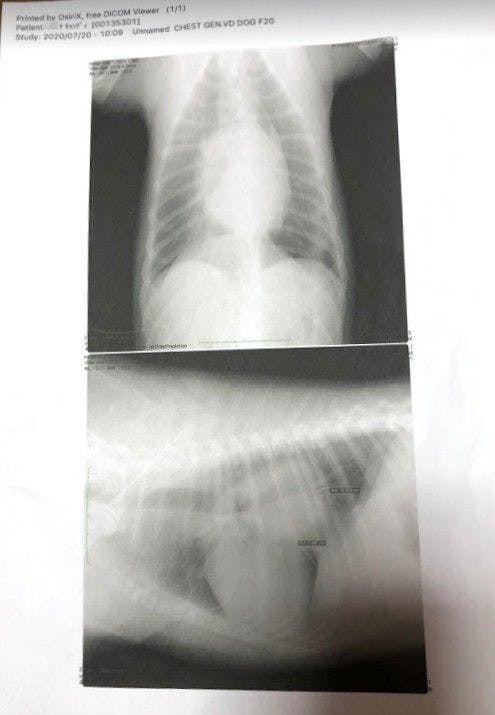

「腫瘍が心臓を圧迫していて左の肺を押しつぶしている為(右肺のみの呼吸)、通常の半分の呼吸しか出来ていず、少し歩くだけでもすぐに苦しくなる状態です。」

とのことでした。